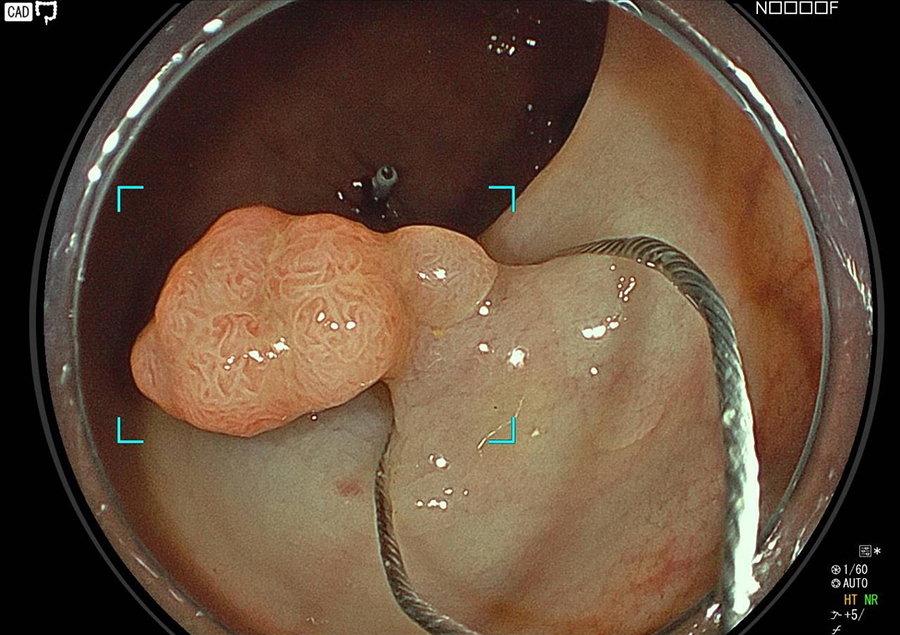

そこで当院では大腸カメラ検査時にポリープや早期がんが発見された場合は、可能な限り積極的にその場で切除しております。

ポリープを切除する時、あるいは切除の数日後に出血することがまれにあり、 出血が多い場合には入院して治療を受けていただくこともあります。

腸の壁の厚さは5㎜しかないので、切除した時に腸に穴を開けてしまう可能性もごくまれに(0.1~0.01%)あります。